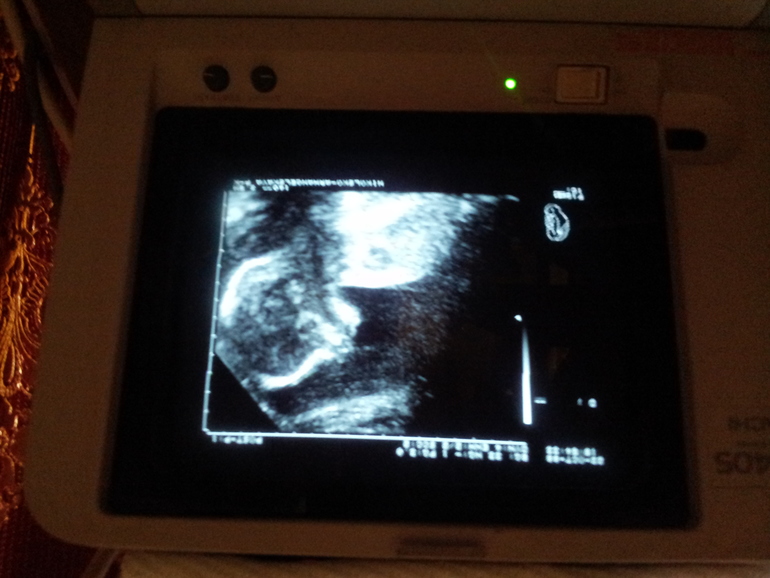

Ну и вот мы в 22 недельки,малыш(на аппарат не обращайте внимания,это у нас поликлинике такая древность))))Ну и собственно сама хозяйка животика,фото на память)